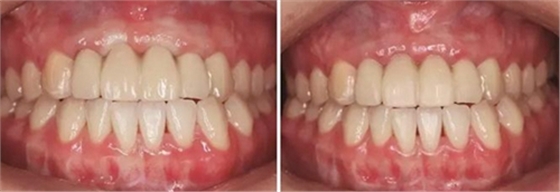

圖37 戴入全瓷修復(fù)體局部舌側(cè)觀 圖38 永久修復(fù)后微笑

圖39 永久修復(fù)后大笑

2、過戴入種植體支持的臨時(shí)修復(fù)體,采用動(dòng)態(tài)加壓技術(shù),獲得了較好的軟組織穿齦輪廓。

3、通過制作個(gè)性化轉(zhuǎn)移桿,將種植體周圍軟組織的形態(tài)輪廓精確地復(fù)制并轉(zhuǎn)移到模型上,個(gè)性化制作的氧化鋯基臺(tái)及全瓷修復(fù)體,生物相容性及美學(xué)效果良好,患者對(duì)最終修復(fù)效果滿意。